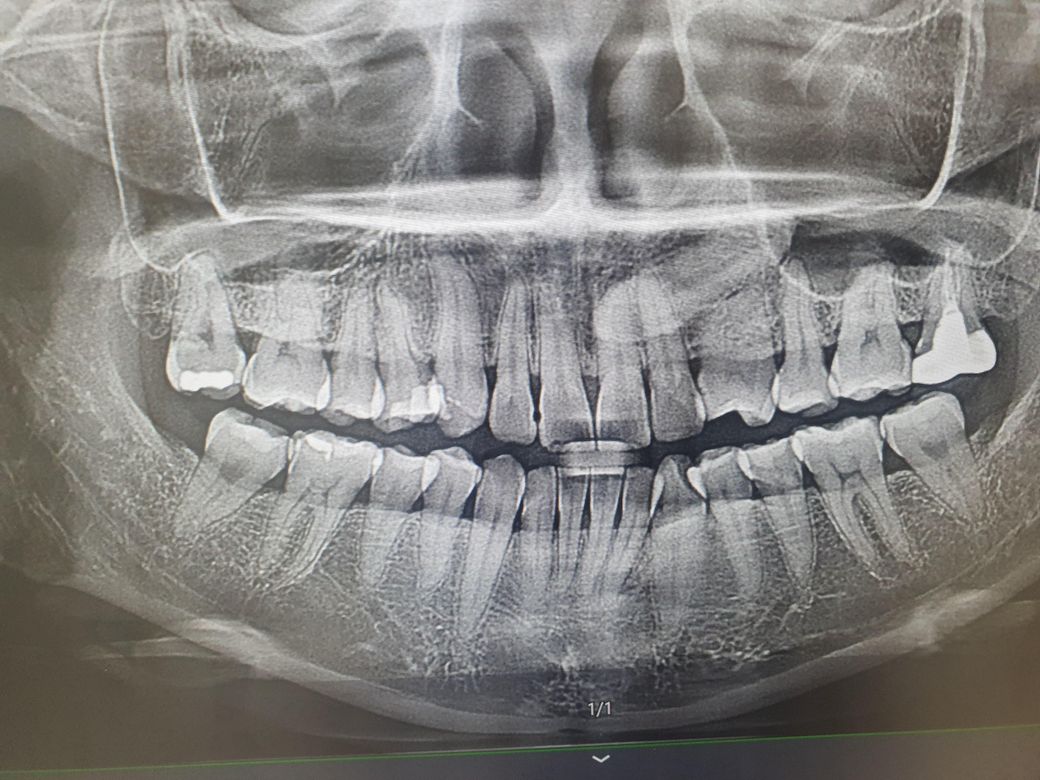

이빨 뿌리끝 염증인지 신경치료말고 주사라던지 해결책있을까요

위 왼쪽에서 두번째이빨 자연치아구요 안쪽에 일자선 있지만 (크랙) 씹을때 불편하지 않았거든요 (부드러운거 위주먹음)

뿌리끝에검한데 잇몸이 안좋대서 스케일링 잇몸치료했는데(그냥 긁어내는데 금방끝나고 깊진않은듯요) 뿌리끝의 염증만 없애는 주사나 이런방법있을까요?저건 잇몸질환 또는 일반치아의 크랙으로 생기는걸까요?(신경치료 안하고싶어서요)

• 1번 째 사진

1. 뿌리주위 염증이 잇몸기원이라면 잇몸치료, 항생제 연고 주사, 약 복용 등이 처치방법입니다

2. 치아기원이라면 신경치료는 불가피합니다